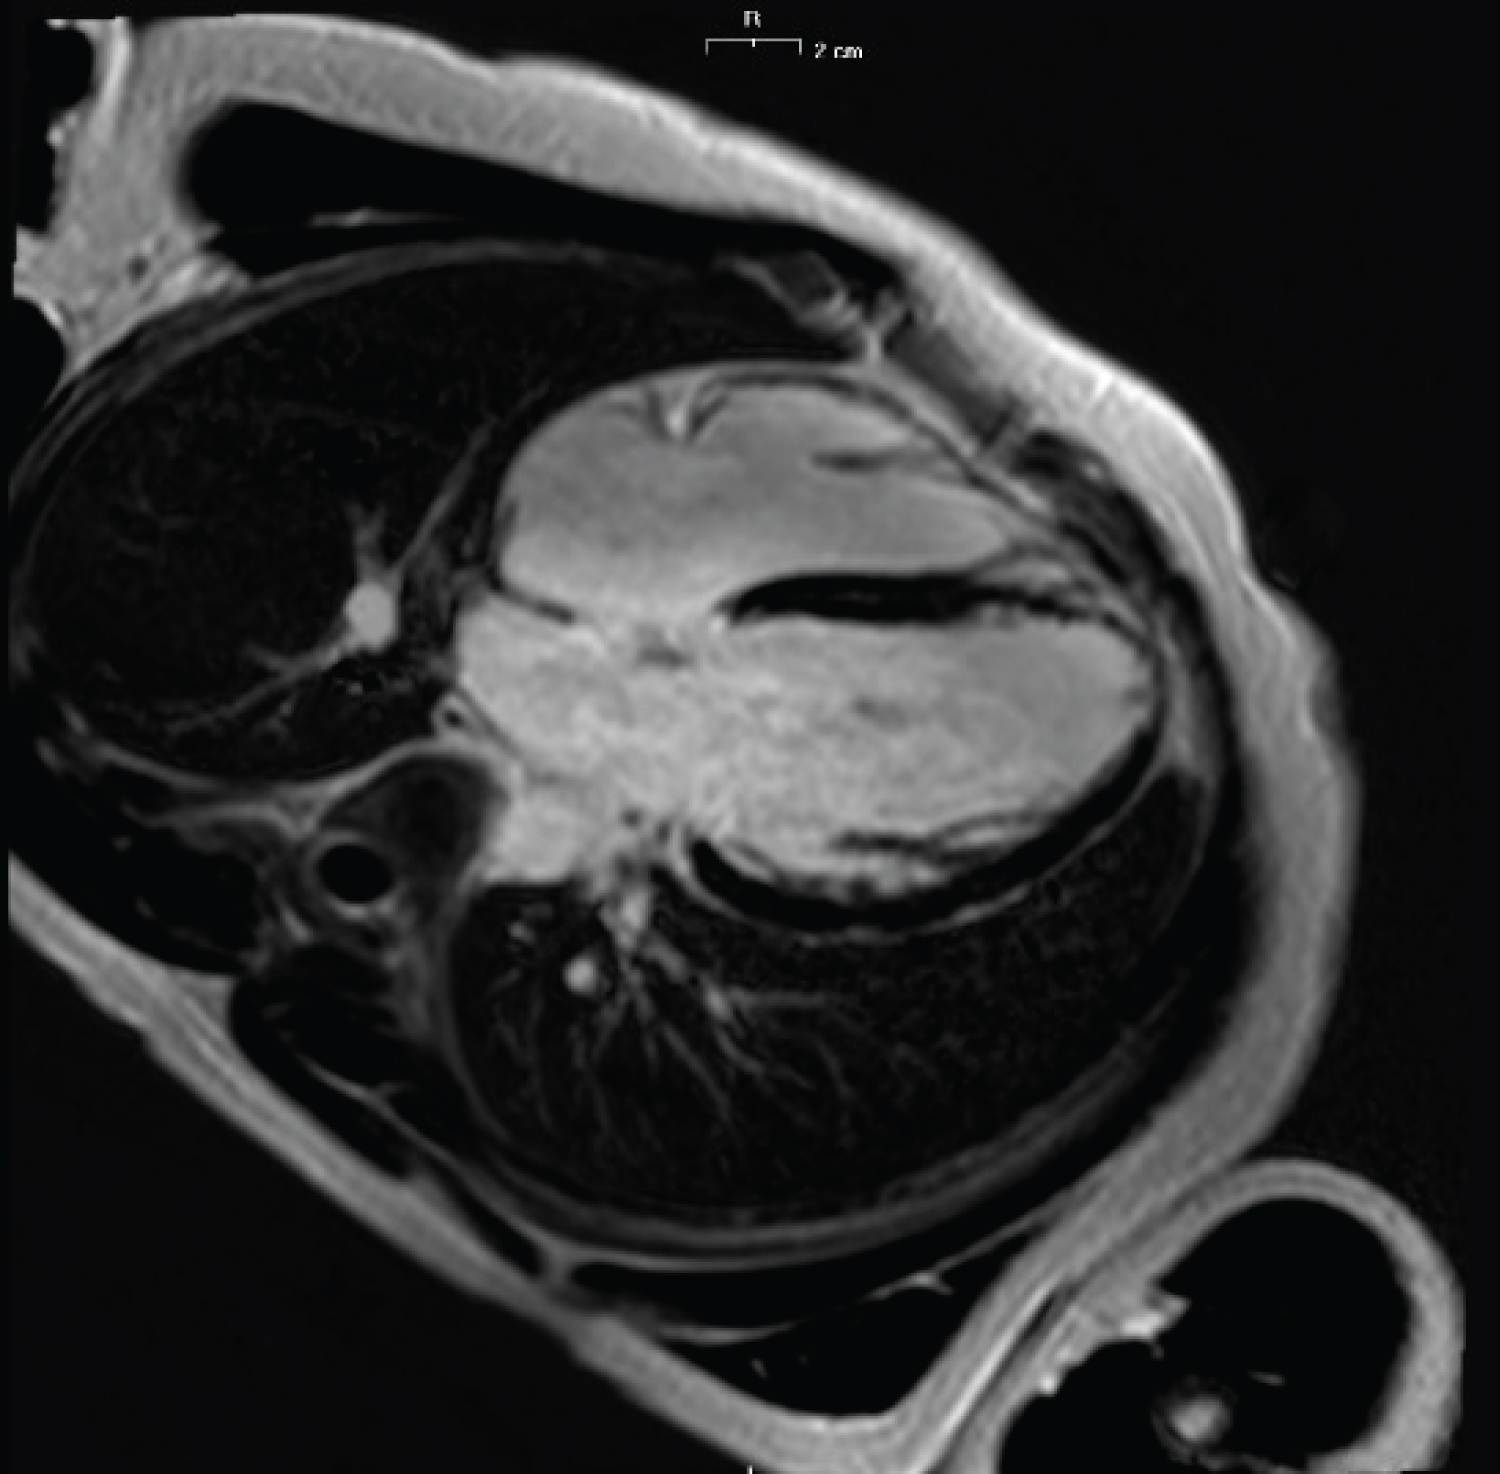

In 2016 a cardiac magnetic resonance showed a slightly dilated left ventricle with a slightly reduced contractile function (Figure 5). Moreover, non-transmural late enhancement of the distal portion of the septal and anterior apex was detected.

Figure 5: Cardiac magnetic resonance shows: Slightly dilated left ventricle; subendocardial late enhancement of the distal portion of the septal and anterior apex. View Figure 5